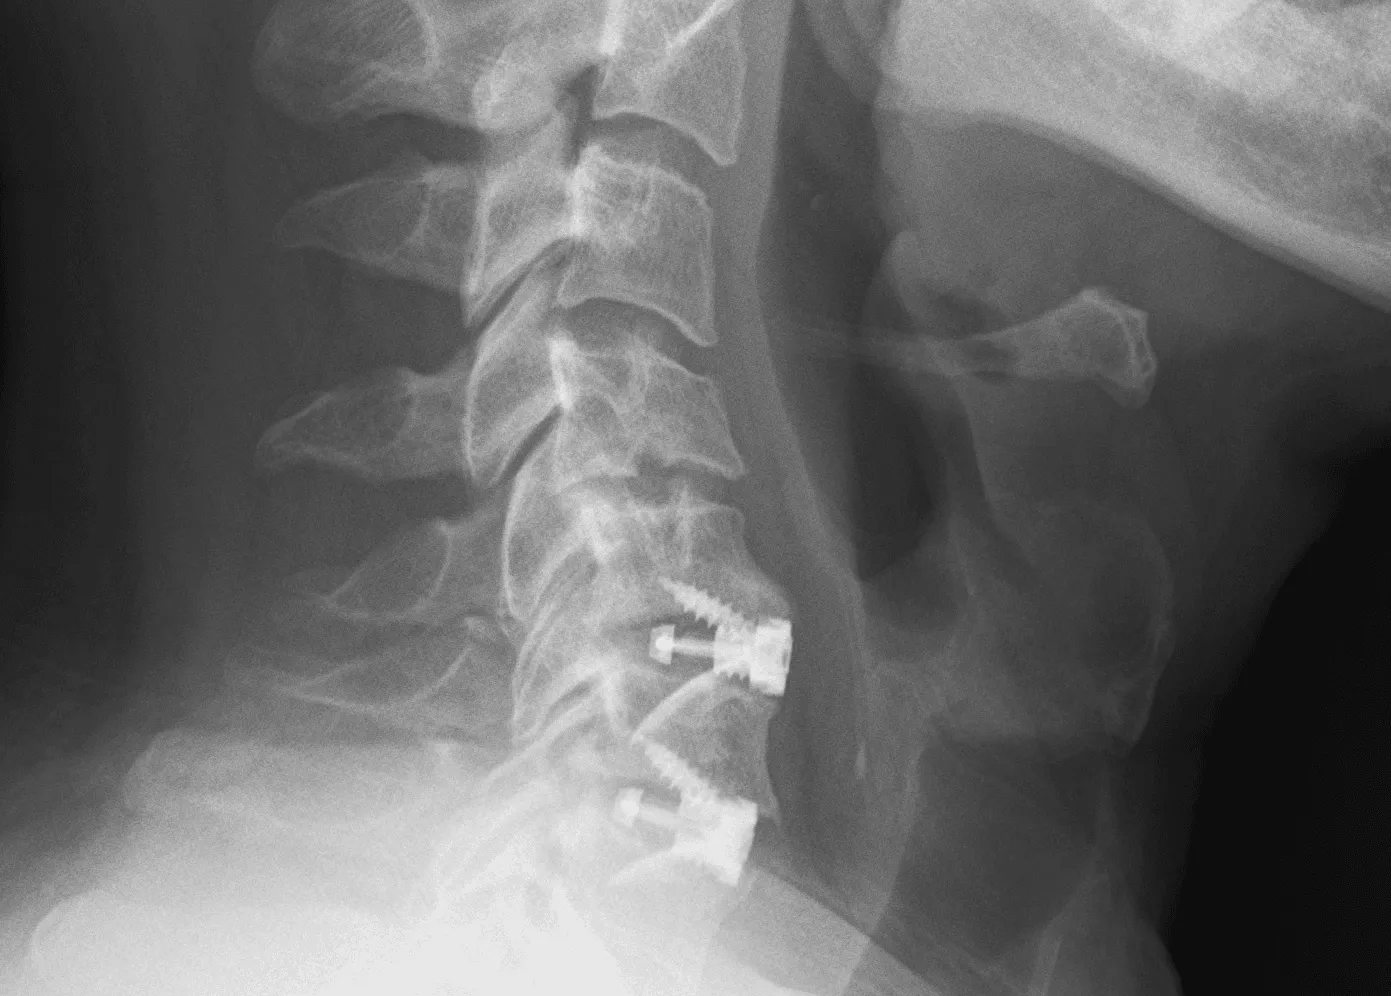

Traditional Fusion Surgery (ACDF)

Anterior cervical discectomy and fusion (ACDF) has been the standard surgical treatment for cervical disc herniation for decades. The procedure involves removing the damaged disc, relieving pressure on the affected nerve or spinal cord, and then permanently fusing the adjacent vertebrae using bone graft and metal hardware. While effective for many patients, fusion permanently limits the neck’s natural range of motion and transfers mechanical stress to adjacent spinal levels. Research has shown that adjacent segment disease requiring reoperation affects approximately 11% of fusion patients, and radiographic degeneration at adjacent levels develops in up to 30%.